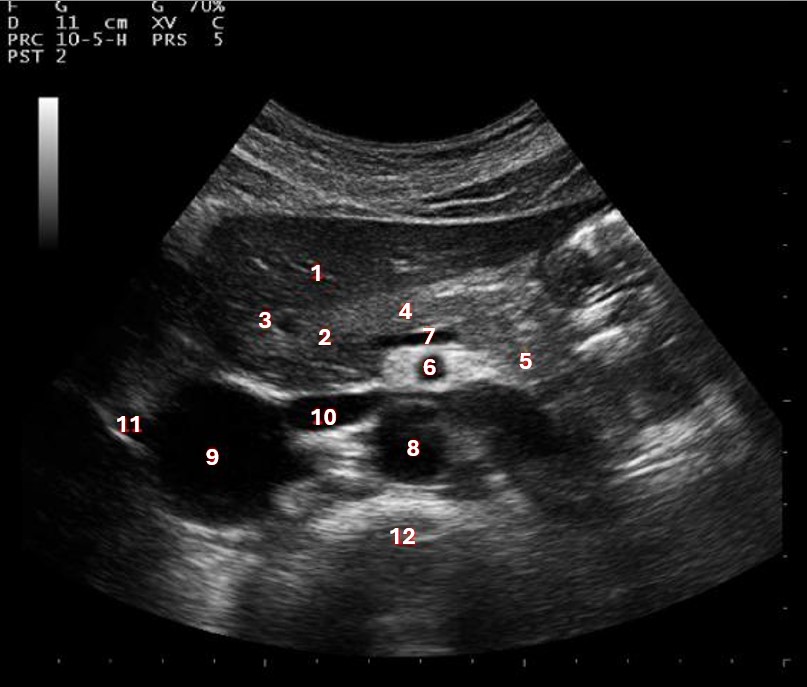

What structure/vessel is indicated by #1?

Medial branch of LPV

What structure/vessel is indicated by #2?

Left portal vein

Which of the following structures is labeled #3?

IVC

Which of the following structures is labeled #6?

Medial left lobe

What structures last vessel is indicated by #4?

Which of the following structures is labeled #4?

Right hepatic vein

Which structure/vessel is indicated by #5?

Lateral left lobe

Which of the following structures is labeled #8?

Posterior right lobe

What structures/vessel is indicated by #5?

Tail of the pancreas

Which structure/vessel is indicated by #4?

Body of the pancreas

What structure/vessel is indicated by #3?

Lateral branch of LPV

What structure/vessel is indicated by #7?

Splenic vein